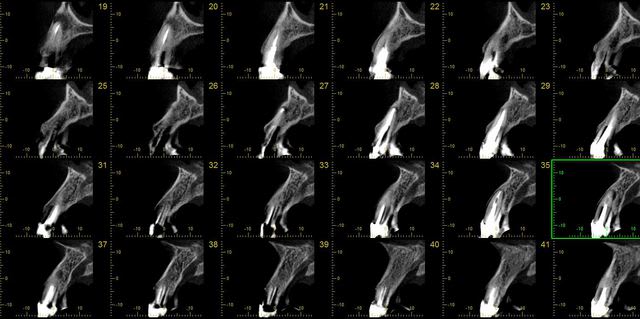

19/12/2012 à 14h27

c'est horrible!

je n’arrête pas de trouver des horreurs aux patients.

en deux jours je viens de découvrir des foyers infectieux carabinés à mes patients. des trucs qui passent complètement inaperçus avec des rétro-alvéolaires.

ici, pensez vous que ce soient les cônes d'argents qui soient en cause ?

Dr guillaumin   implantologie pawiqq - Eugenol

Guillaumin   mondelange   implants 2 u1mwiz - Eugenol

possible...y en a qui dépassent...

mais y a pas aussi une perfo ou une résorption interne sur la dent?